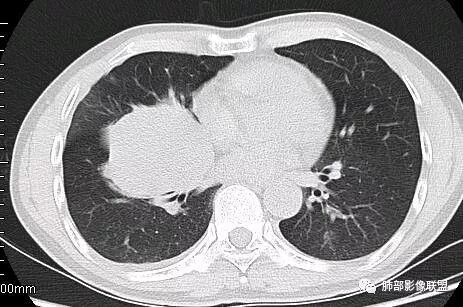

这一个类圆形,边界光滑,明显膨胀生长为主,如果起源中叶支气管,按理中叶支气管不动,固定在中叶支气管上,推移其他结构

但是现在的片显示,其主体在下叶,中叶支气管壁由下朝上有推移

南边:就不符合这个原理

初学者:如果中叶病灶,叶间裂应该下推,也不会上推

南边:从叶裂的变形,下朝上,越来越朝前扭曲,提示叶裂局部有朝前上推移的趋势

南边:下叶的支气管受压后移、变形

南边:病灶边界清,提示侵袭性弱,膨胀生长为主;这时候我们提示病灶不应该是支气管关系密切,提示间叶来源或胸膜来源